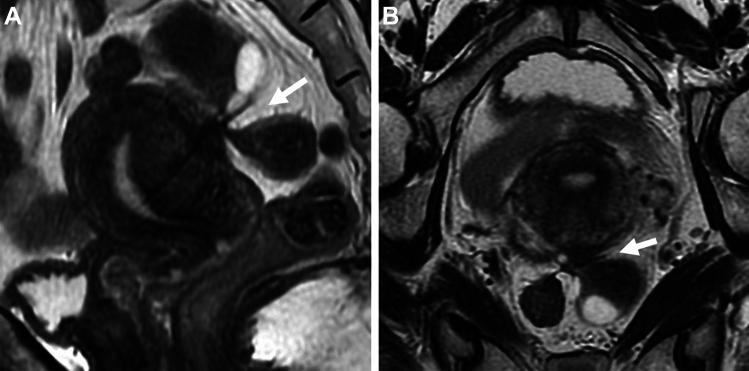

Endometriosis is a benign, common, but controversial disease due to its enigmatic etiopathogenesis and biological behavior. Recent studies suggest multiple genetic, and environmental factors may affect its onset and development. Genomic analysis revealed the presence of cancer-associated gene mutations, which may reflect the neoplastic aspect of endometriosis. The management has changed dramatically with the development of fertility-preserving, minimally invasive therapies. Diagnostic strategies based on these recent basic and clinical findings are reviewed. With a focus on the presentation of clinical cases, we discuss the imaging manifestations of endometriomas, deep endometriosis, less common site and rare site endometriosis, various complications, endometriosis-associated tumor-like lesions, and malignant transformation, with pathophysiologic conditions.